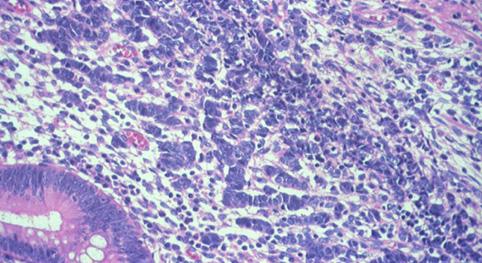

A case of an nodule-aggregated tumor with adenocarcinoma which developed in the cecum (1990's).

Tokyo Pref., Cooperative study between National Cancer Center and Kyushu Cancer Center

Large intestine(Colon)/Cecum

Histology

Type 0/Others

20 - 24

submucosa